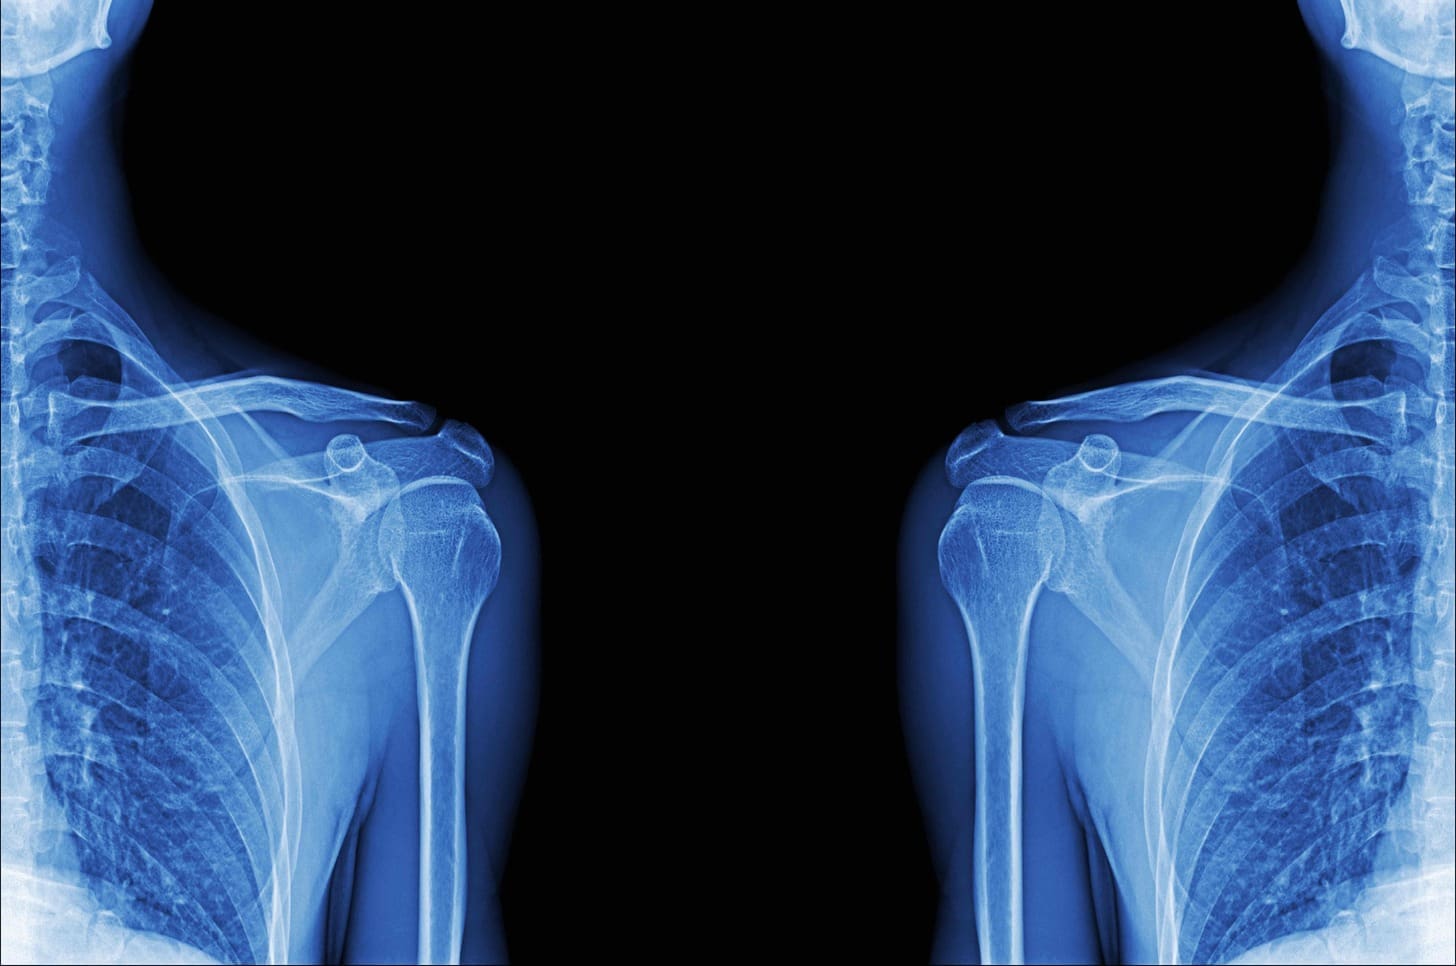

Specific Bone Types and MRI Benefits

MRI is very good at showing different bones clearly. It’s great for finding fractures in certain bones. We’ll look at how MRI helps with spinal, small-bone, and complex joint fractures.

Spinal Fractures and Vertebral Injuries

MRI is great for checking spinal fractures and injuries. It shows the spine well, spotting fractures and soft tissue problems. It’s key toseeing the spinal cord and other important areas.

Some benefits of MRI for spinal fractures are:

- Detailed views of the spine and discs

- Finding spinal cord problems

- Seeing ligament injuries or instability

Complex Joint Fractures

Complex joint fractures are hard to diagnose with regular images. MRI gives a full view of the joint, including bones, ligaments, and cartilage. This info is key for surgery and recovery plans.

Key MRI benefits for complex joint fractures are:

- Full check of the joint

- Finding soft tissue injuries

- Helping with surgery and recovery

In summary, MRI is very helpful for diagnosing specific bone injuries. It’s great for spinal, small bone, and complex joint fractures. Its detailed images of bones and soft tissues make it essential in orthopedic care.